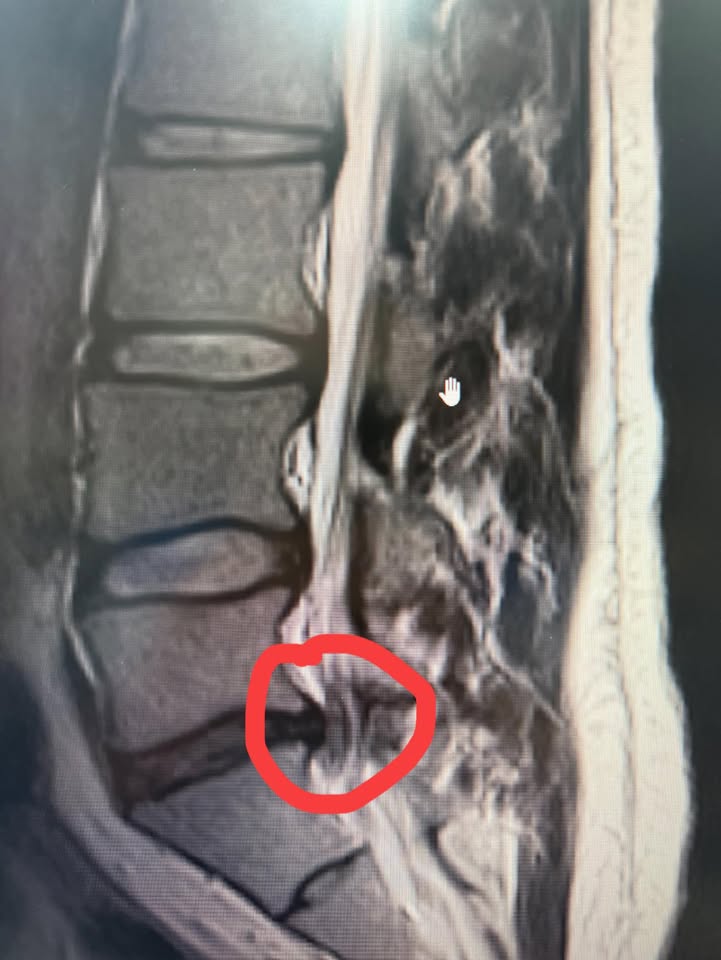

初步檢查後,我發現黃先生的疼痛並非單純的肌肉問題,懷疑是腰椎結構異常所導致的神經壓迫。為了進一步確認診斷,當天便安排了核磁共振(MRI)檢查,結果顯示:

• L5(腰椎第五節)椎間盤退化,伴隨脫水與

輕微狹窄

• 椎間盤突出壓迫神經,是導致持續疼痛的

主因